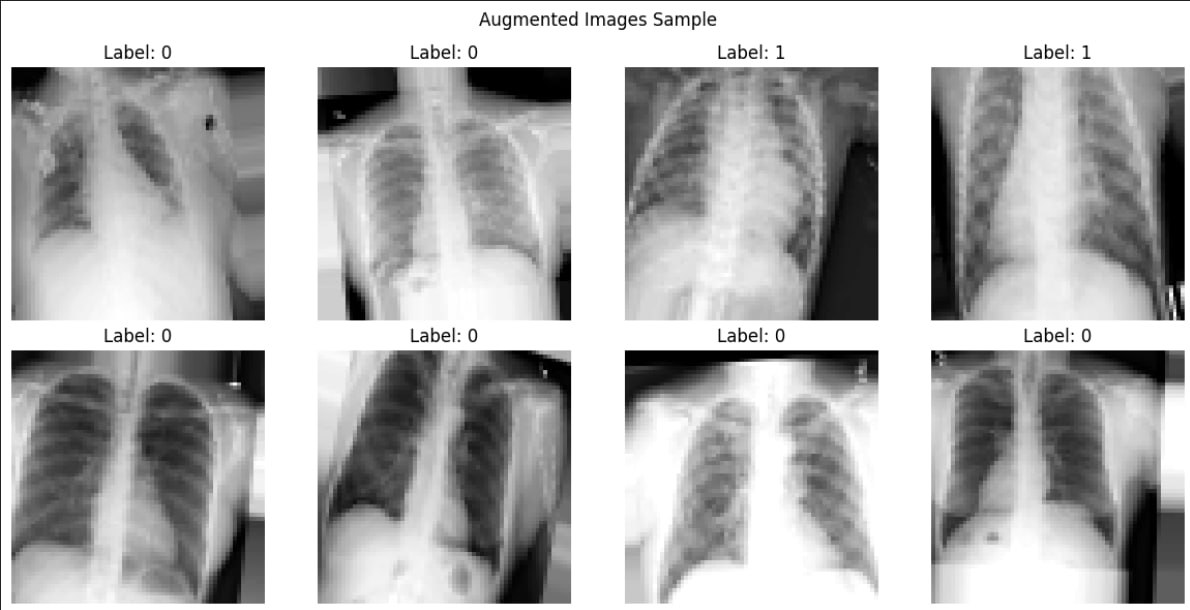

Model classification CNN Pneumonia

- Basic ML implementations